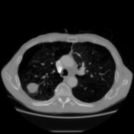

Aside from quantitative results, we provide a principal component analysis (PCA) of the embeddings of Merlin, CT-FM, CT-CLIP, and our COLIPRI encoders, on a lung cancer case from the MSD Lung dataset (Fig. 6).

The resolution of the embeddings of Merlin and CT-FM is very low, providing hardly any localisation of semantics. CT-CLIP yields embeddings of higher resolution, allowing one to map the features from the input chest CT to the PCA map. However, the PCA is inconsistent and noisy, and shows high sensitivity to air in its principal components, and a strong bias towards position embeddings. On the other hand, our COLIPRI encoders yield higher-resolution embeddings, which are sharper and more consistent, allowing for clear recognition of the boundaries of the patient, lungs, and the abdominal organs, as well as the lung mass present in the right lung (on the left-hand side of the coronal and axial slice views).